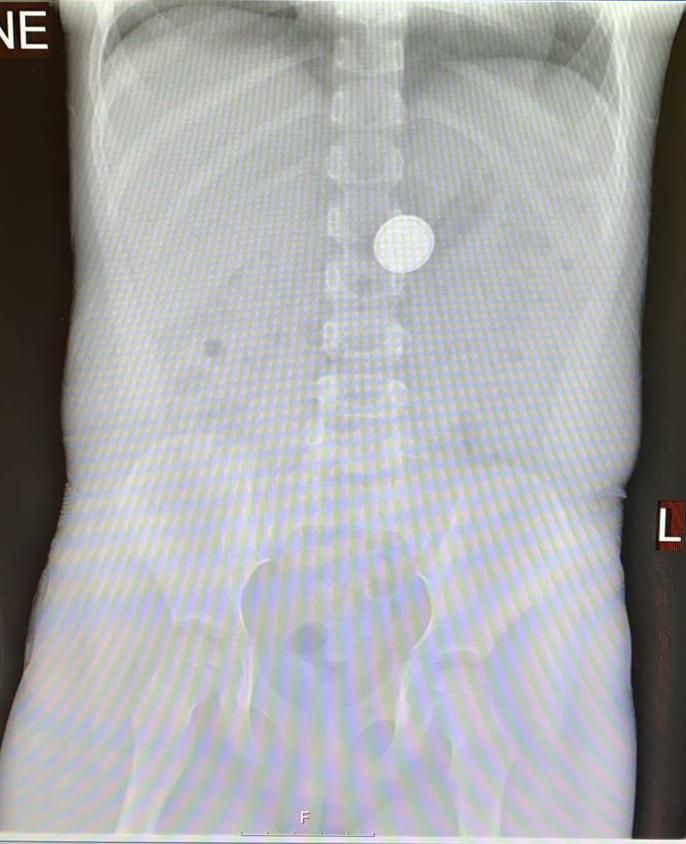

"הנזק הפוטנציאלי של סוללה נובע ממספר גורמים: לחץ מכני על איברים פנימיים, כמו במקרה של בליעת מטבע, הפעלת זרם חשמלי כתוצאה ממגע של דפנות מערכת העיכול עם שני הקטבים של הסוללה ודליפה של תוכן הסוללה (הסוללות מכילות בסיס חזק וכן מתכות כבדות כמו כספית, כסף, ליתיום)".

"במידה והסוללה תקועה בוושט, מדובר במצב חרום הדורש הוצאה מידית של העצם הזר ללא קשר אם הילד סימפטומטי. סוללות מסוג מסוים מצריכות התערבות פולשנית גם אם כבר הגיעו לקיבה. מדובר בפירוש במצבים שעלולים להגיע למצב מסכן חיים".